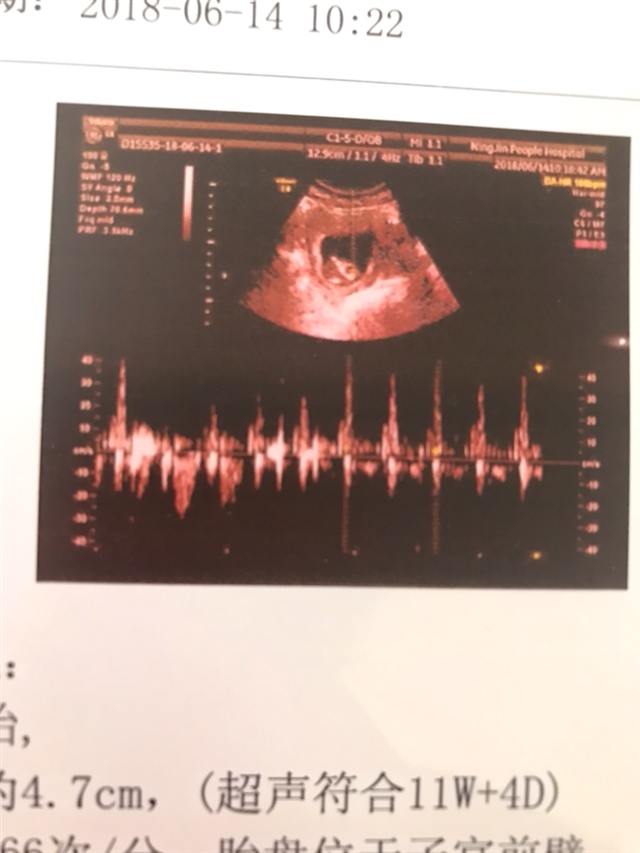

怀孕 孕7周+6天